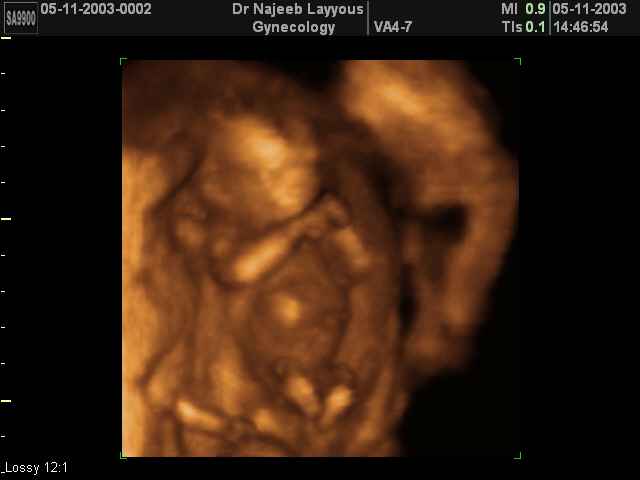

Stuart Campell, a former abortionist who developed 3-D ultrasound, describe the impact that seeing the unborn baby on the ultrasound screen had for him:

“I think you’re programmed into just doing it as a job. The doctor is not around to see the baby being expelled. My job was to inject the foetus’s heart. You’ve got a hundred other things to do that day so you just go ahead and do it. But with the traditional 2-D scanning I think you are less connected with the reality of what you’re doing than you would be with these new techniques.”

“The hidden wonder of new life” The Tablet July 10, 2004